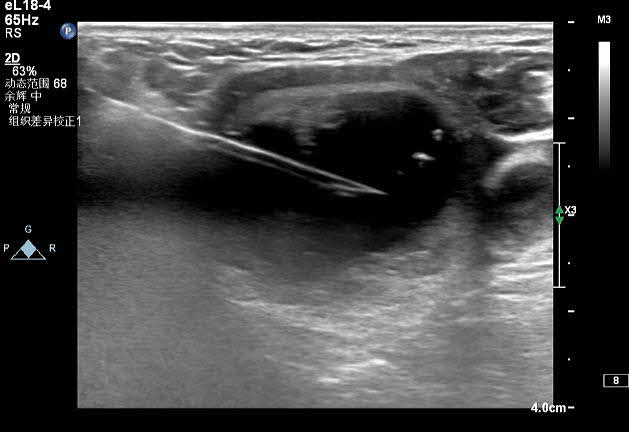

王女士在半年前因颈部包块就诊于我院,超声提示甲状腺左叶囊实性包块,因疫情原因未进一步治疗;近半年来包块明显增大,颈部膨隆,为进一步治疗就诊于我院血液内分泌科。彩超诊断为甲状腺左侧叶囊实性结节,患者因惧怕疼痛,不愿手术,选择保守治疗;后得知甲状腺结节可以超声引导下微创治疗,遂联系超声科进行咨询;超声科医生对王女士的甲状腺结节进行评估后,就射频消融术的优点、术前的准备、术中的风险、术后的注意事项详细讲解,王女士当即决定选择射频消融术治疗甲状腺结节。4月9日下午在介入超声手术室顺利完成手术,术后颈部仅一个针眼大小。术中囊性部分抽吸为黑红色粘稠液,实性部分消融治疗,术后即刻造影结节内未见造影剂回声。

对结节实性部分进行移动式+固定式射频消融